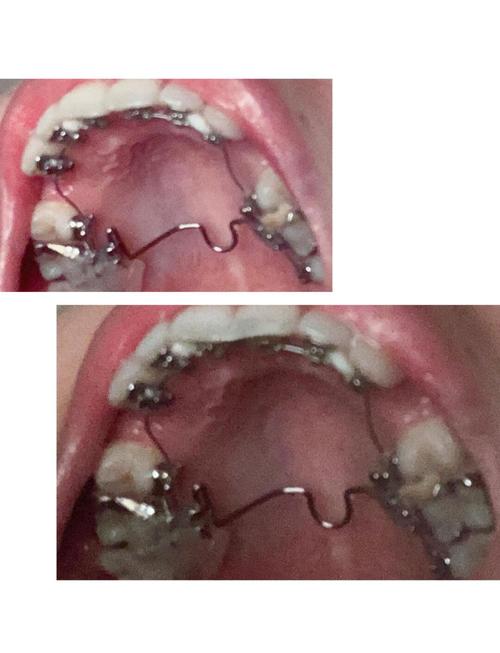

- 极致美观: 这是舌侧矫正最大的吸引力,托槽和弓丝完全隐藏在牙齿内侧,从外面完全看不到,对于32岁这个职场社交活跃的年龄,美观需求非常高,舌侧矫正能让你在矫正过程中完全不用担心“钢牙”形象,工作、社交、拍照都非常自信。

- 个性化定制: 舌侧托槽通常是间接粘接的,需要取模后由技师在模型上精确粘好托槽,然后由医生转移到你口内,这种定制化方式能更精确地控制牙齿移动,理论上可以达到非常精细的矫正效果。

- 粘接难度大: 舌侧托槽粘接在牙齿内侧,视野受限,操作空间小,对医生的技术和经验要求极高,选择一位经验丰富、专门从事舌侧矫正的医生是成功的关键,操作不当会导致托槽脱落频繁、效率低下、甚至损伤牙齿。

- 舌头刺激: 舌头不断接触内侧的托槽和弓丝,初期会有明显的异物感、刺痛感、溃疡,影响说话、吞咽和进食,需要一段时间的适应(通常1-2周)。

- 口腔清洁难度大: 舌侧矫正的清洁比传统矫正和隐形牙套都困难得多,托槽和弓丝在牙齿内侧,牙刷很难有效清洁,容易堆积食物残渣和菌斑,大大增加蛀牙和牙龈炎的风险,需要学习并严格执行非常细致的清洁方法(如使用正畸专用小头牙刷、牙缝刷、冲牙器、牙线牵引器等),并定期进行专业洗牙。